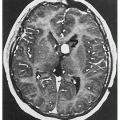

![]() 3.2. MRI with gadolinium revealing leptomeningeal malformation. (5) |

![]() 3.11. MRI shows four enhancing cerebellar hemangioblastomas. (36) |